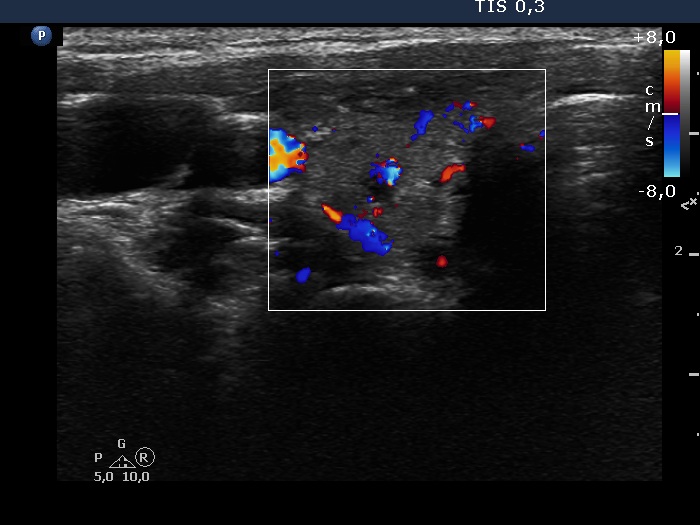

Thyroid cancers - case 2221 (ultrasonographic picture 3)

Right lobe, transverse scan, color Doppler mode. The vascularization is average.